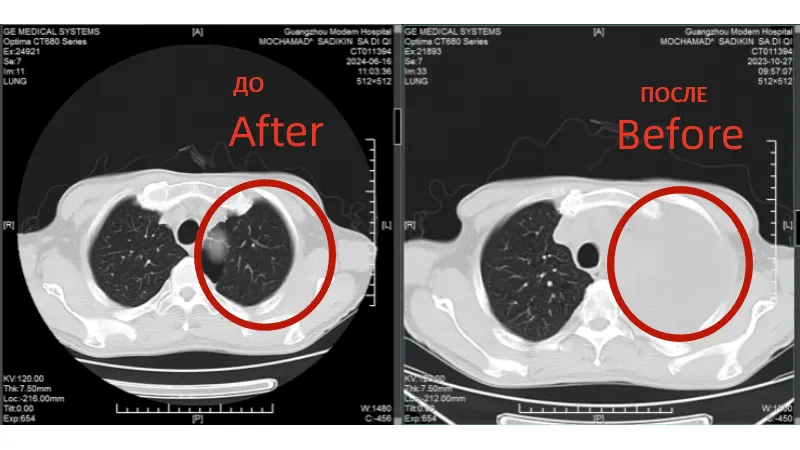

КТ-снимки подтвердили: динамика положительная, болезнь отступает

26 февраля 2024 года результаты КТ показали, что опухоль легкого значительно уменьшилась

Результат: победа над невозможным

• Через 2 месяца: Опухоль в легком практически исчезла, метастазы в лимфоузлах значительно уменьшились. • Сердечная функция стабилизировалась - лечение не усугубило риски. • Возврат к активной жизни: Рамли общается с пациентами из других стран, используя переводчик, и вдохновляет их своим примером.